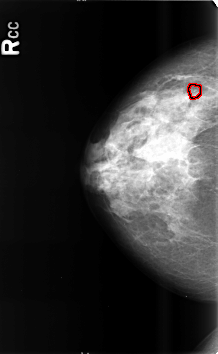

B_3464_1.RIGHT_CC

FILE: B_3464_1.RIGHT_CC.OVERLAY

TOTAL_ABNORMALITIES 1

ABNORMALITY 1

LESION_TYPE CALCIFICATION TYPE AMORPHOUS-PLEOMORPHIC DISTRIBUTION CLUSTERED

ASSESSMENT 4

SUBTLETY 3

PATHOLOGY BENIGN

TOTAL_OUTLINES 1

BOUNDARY

RIGHT_CC LINES 4600 PIXELS_PER_LINE 2824 BITS_PER_PIXEL 12 RESOLUTION 50 OVERLAY